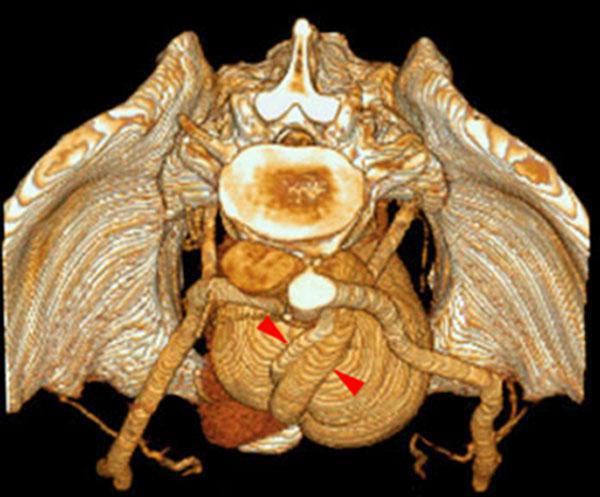

Hipoplasia renal 1